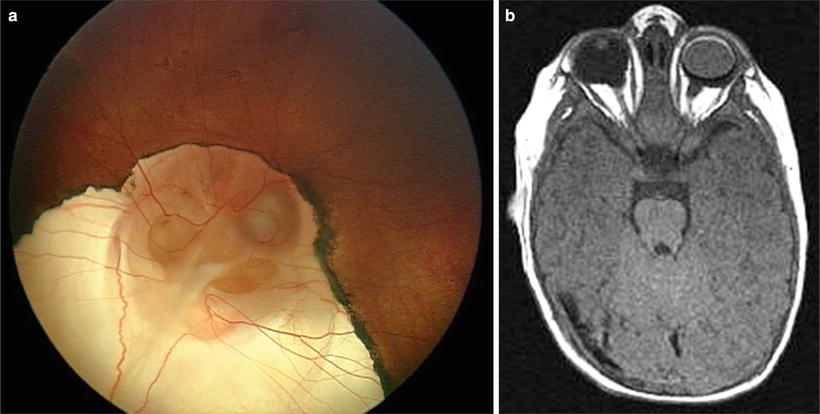

Cerebral hemispheric abnormalities associated with optic nerve hypoplasia. (a) Axial T1-weighted inversion recovery MR image demonstrating schizencephaly in patient with optic nerve hypoplasia. Schizencephalic cleft (arrows) consists of abnormal band of dysmorphic gray matter in left cerebral hemisphere extending from cortical surface to lateral ventricle. (b) T2-weighted axial MR image demonstrating asymmetrical periventricular leukomalacia, worse in right hemisphere (left side of picture), in child with optic nerve hypoplasia. Note enlargement and irregular contour of posterior aspect of lateral ventricle. Black arrow denotes loss of posterior periventricular white matter, with direct apposition of cortical gray matter to trigone of lateral ventricle. White arrow indicates greater volume of posterior periventricular white matter in the left hemisphere. With permission, from Brodsky and Glasier [58]. Copyright 1993, American Medical Association.